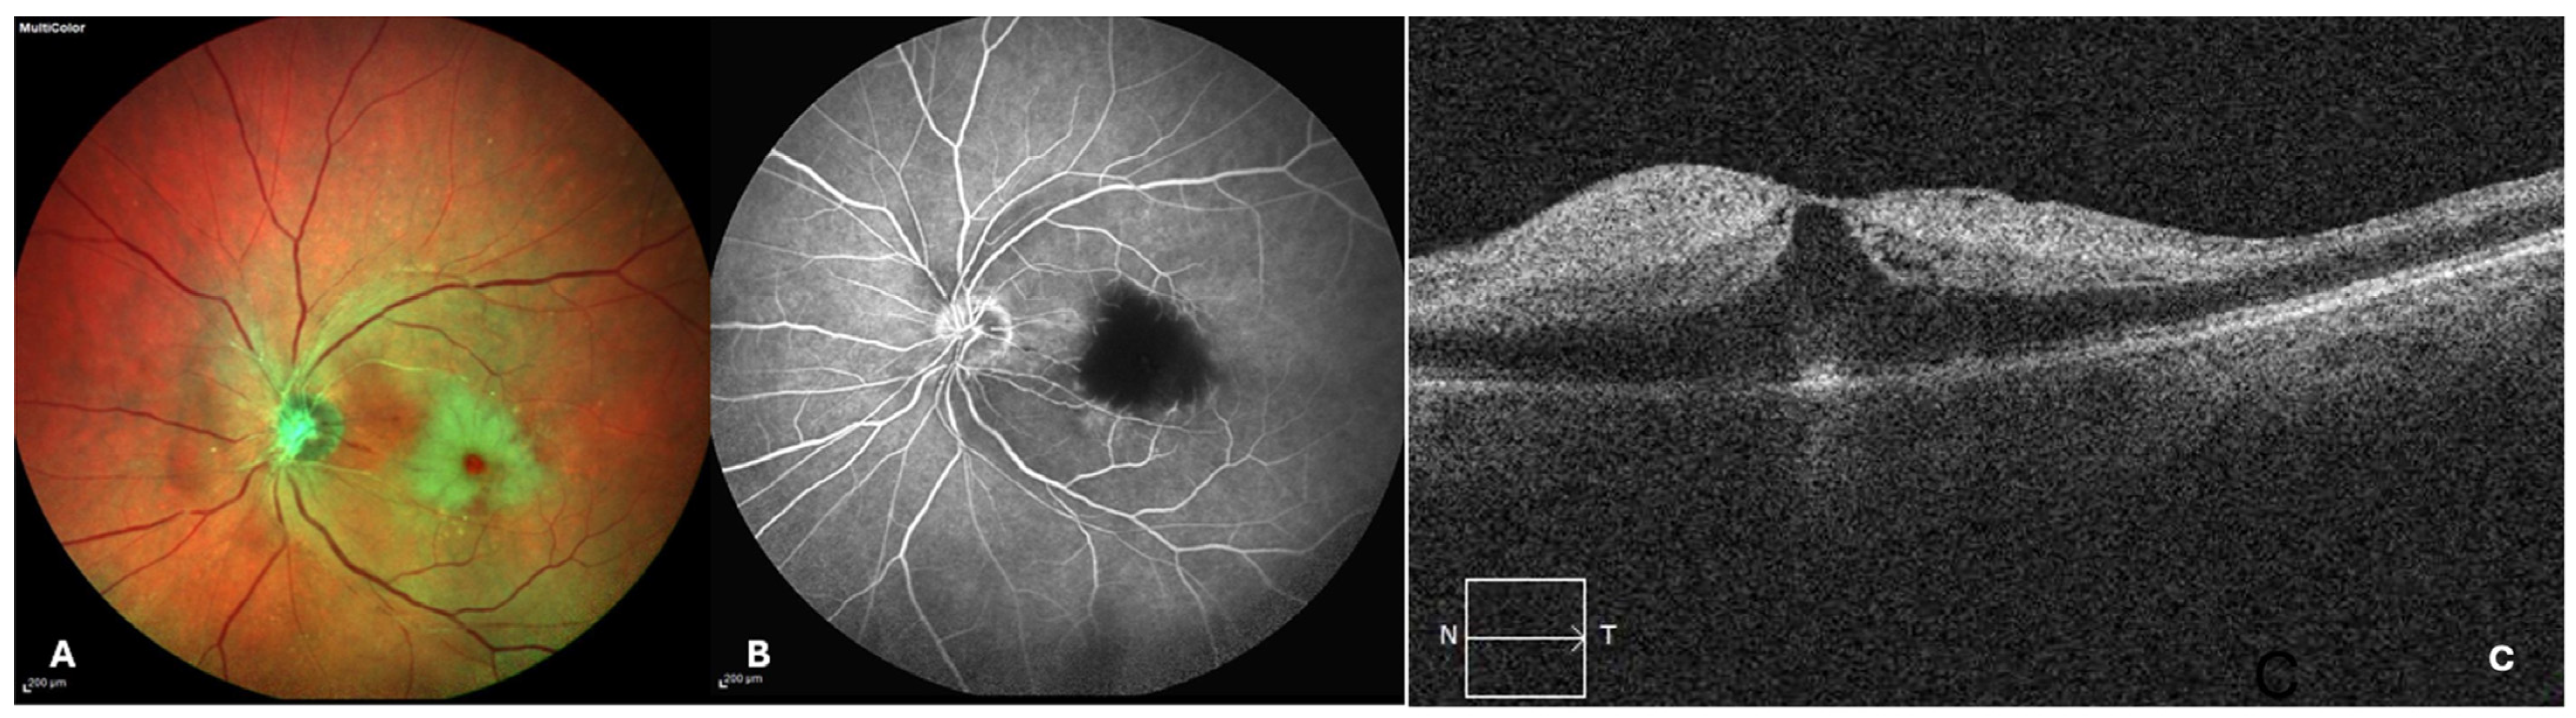

| Gabrielian et al. (2009) | [39] | Case report | 1 case | A healthy 17-year-old male presented with sudden, painless loss of vision in his right eye while playing basketball. Fundus examination and fluorescein angiography confirmed a retinal artery occlusion. The hematological/infectious work-up, including TTE, was negative. However, TEE showed PFO. The patient underwent a successful percutaneous femoral catheterization to close the defect. |

| Pipolo et al. (2023) | [51] | Case report | 1 case | A 28-year-old woman presented at the clinic 20 h after an acute visual field defect in the right eye. At that time, she was 18 weeks pregnant and had no report of complications in her previous pregnancy. After ophthalmological evaluation, BRAO was diagnosed. A transcranial Doppler with contrast indicated a right-to-left intracardiac shunt, confirmed by the presence of PFO at the TEE. Thrombophilic conditions were excluded. Enoxaparin 1 mg/kg was started and kept until the delivery. Then, a surgical closure of PFO was programmed. |